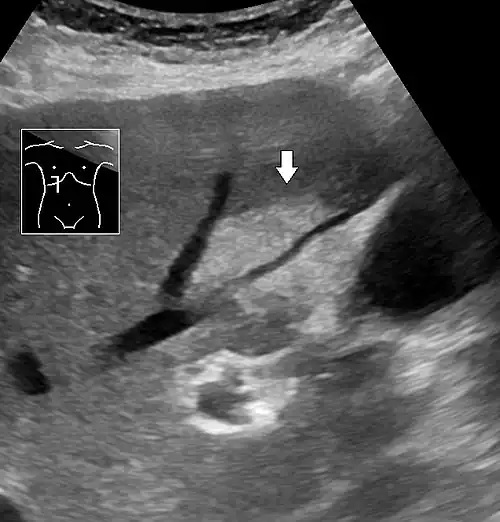

Medical imaging

On X-ray computed tomography (CT), the increased fat component will decrease the density of the liver tissue, making the image less bright. Typically the density of the spleen and liver are roughly equivalent. In steatosis, there is a difference between the density and brightness of the two organs, with the liver appearing darker.[12] On ultrasound, fat is more echogenic (capable of reflecting sound waves). The combination of liver steatosis being dark on CT and bright on ultrasound is sometimes known as the flip flop sign.

On abdominal ultrasonography, steatosis is seen as a hyperechoic liver as compared to the normal kidney.